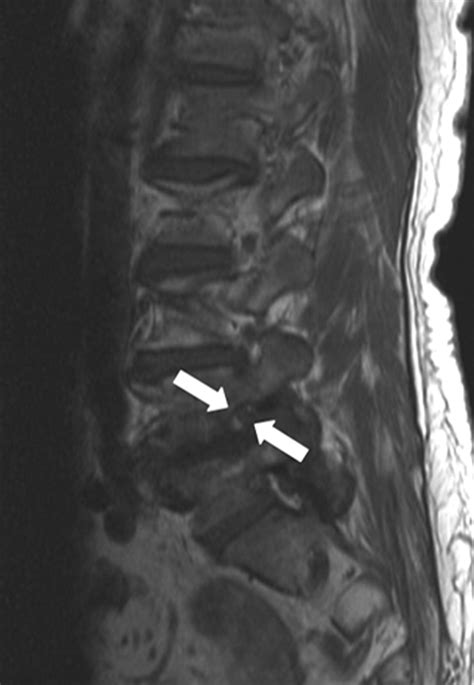

To confirm Severe Bilateral Foraminal Stenosis, medical professionals rely on advanced imaging and clinical evaluation. Physical examinations typically focus on testing reflexes, muscle strength, and dermatomal sensitivity to identify which nerve roots are being compromised. Once a clinical suspicion is formed, imaging is utilized to provide a roadmap of the spinal canal.

The gold standard for diagnosis is an MRI (Magnetic Resonance Imaging) scan. Unlike X-rays, which only show bone, an MRI provides a detailed cross-sectional view of soft tissues, nerves, and discs. It allows the surgeon to visualize the exact degree of narrowing at each level of the spine. In cases where an MRI is not possible, a CT myelogram may be used to see how the spinal fluid flows around the nerves.